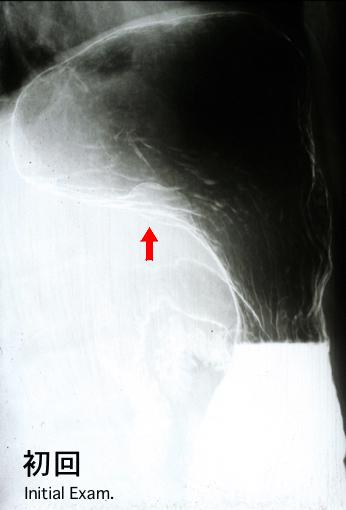

3년 3개월간에 약 2.5배 증대한 위의 평활근육종

악성 비상피성종양/평활근육종

위(부위)/체부

X-P

10~14